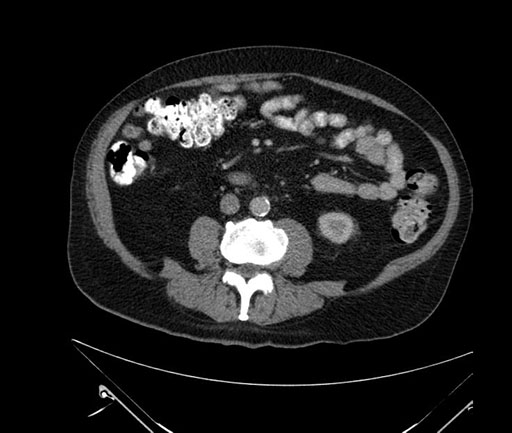

Whipple (pancreaticoduodenectomy) [case 7]

Imaging Analysis

Look through the patient's CT scan to identify any areas of concern for the necessary procedure.

Coronal - stented